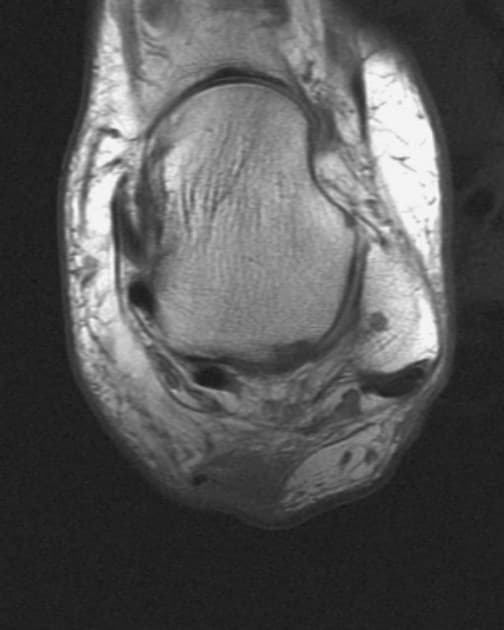

Bucket Handle Meniscal Tear of the Medial Meniscus (Vết rách sụn chêm dạng xô gánh)